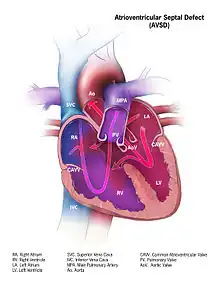

Complete AVSD with mixed oxygenated and deoxygenated blood entering both the aorta and the pulmonary arteries.

Defective embryonic formation of the heart results in multiple holes between the heart chambers. In AVSD, all four chambers are connected, but the exact characteristics of holes and malformations may vary between patients. Even within the categories of "complete" and "partial" AVSD, multiple morphologies exist, with varying clinical consequences. Clinical and physiological manifestations of disease may also change over time, in response to continued stress.[3]